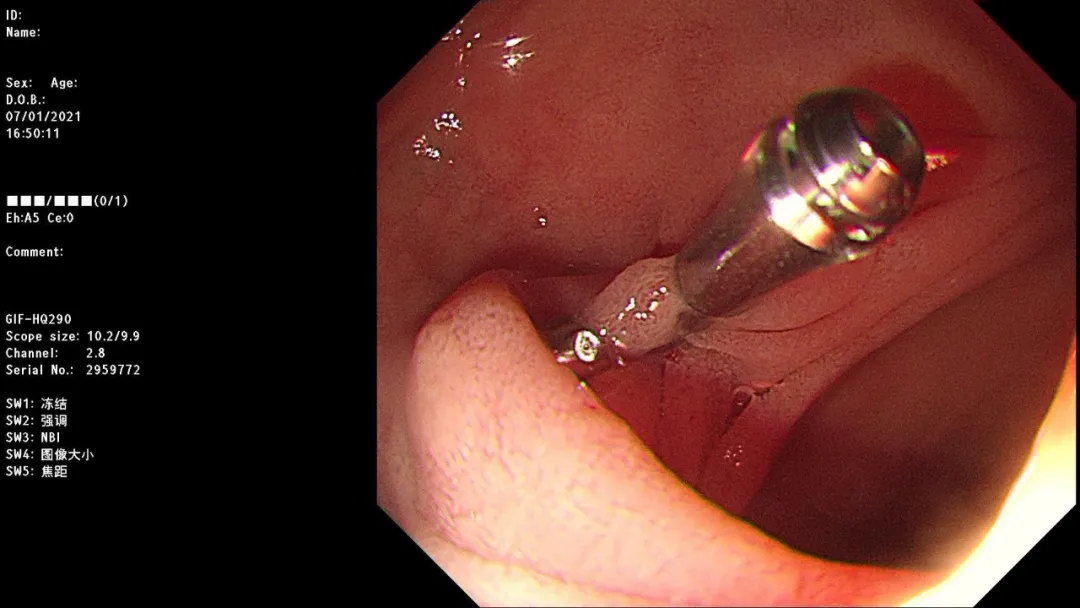

急诊胃镜示:十二指肠降段活动性渗血,予钛夹夹闭,检查诊断:十二指肠降段多发血管畸形并出血急诊钛夹止血术。